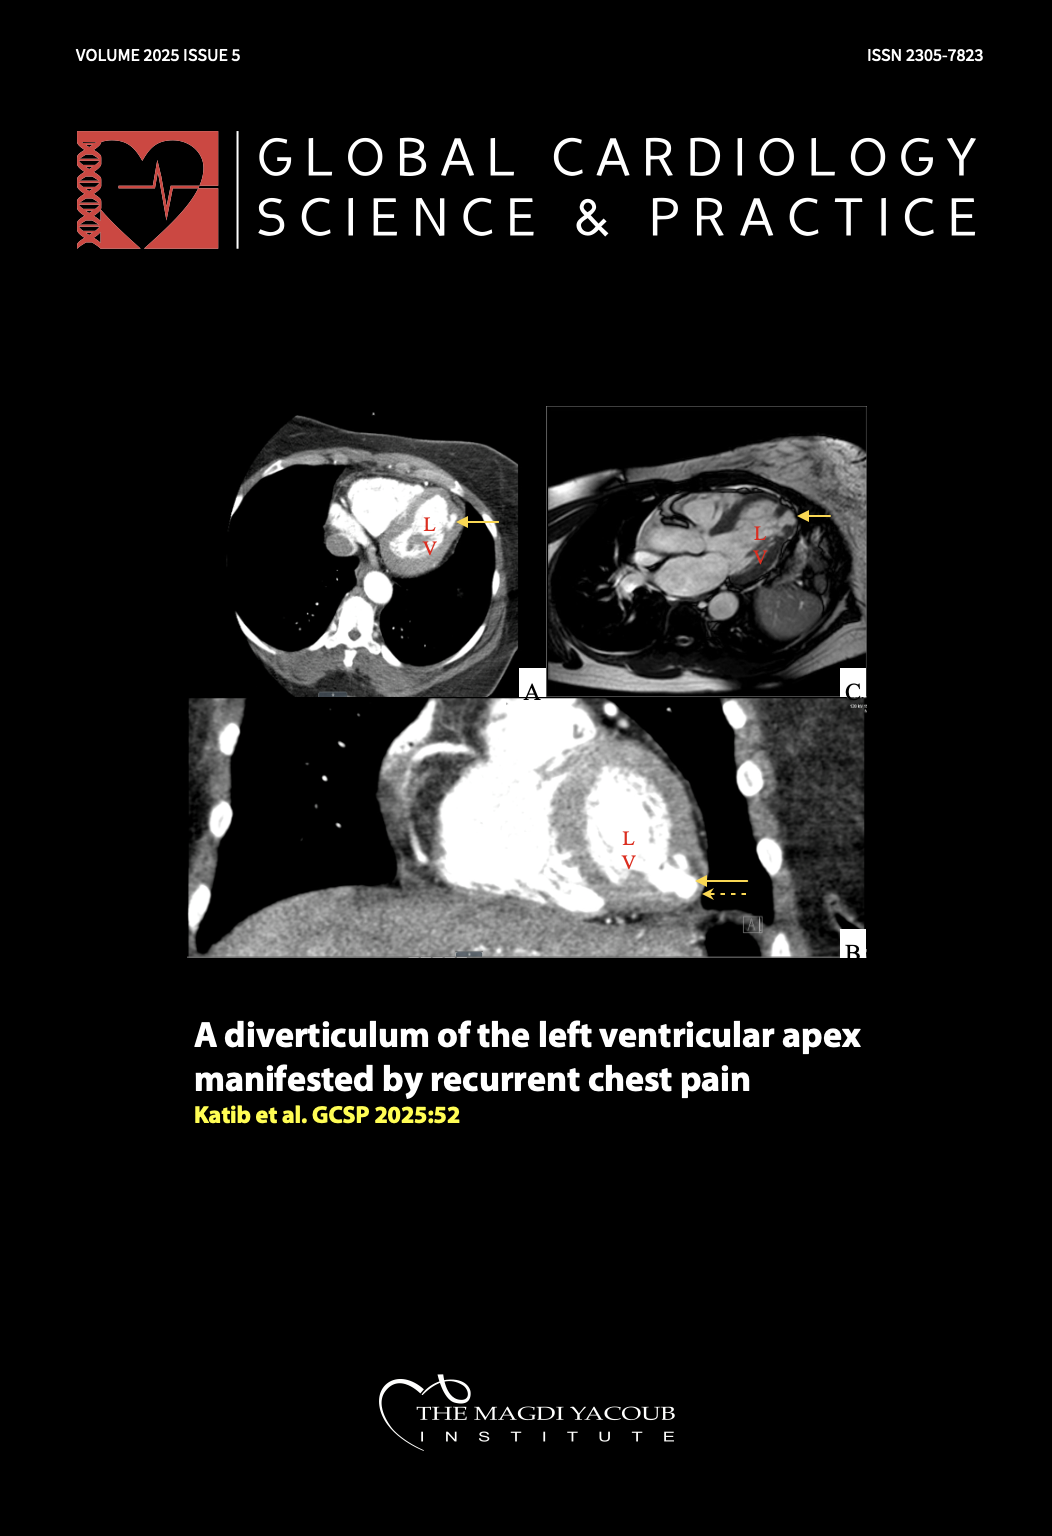

A diverticulum of the left ventricular apex manifested by recurrent chest pain

Husam Katib, Sarah Alem, Nawfal Alkhafaji, Hamza Yousaf, Manoj Sharma